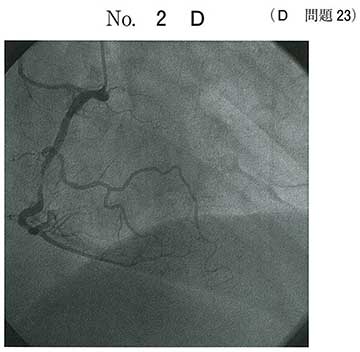

uAP患者

LMT及びRCAに狭窄あり。PCIは無理

3本狭窄 a

右冠動脈と左冠動脈本幹の狭窄だと思います。

バイパス術の適応。

AVR誘導のST上昇は左主幹部病変をまず考える